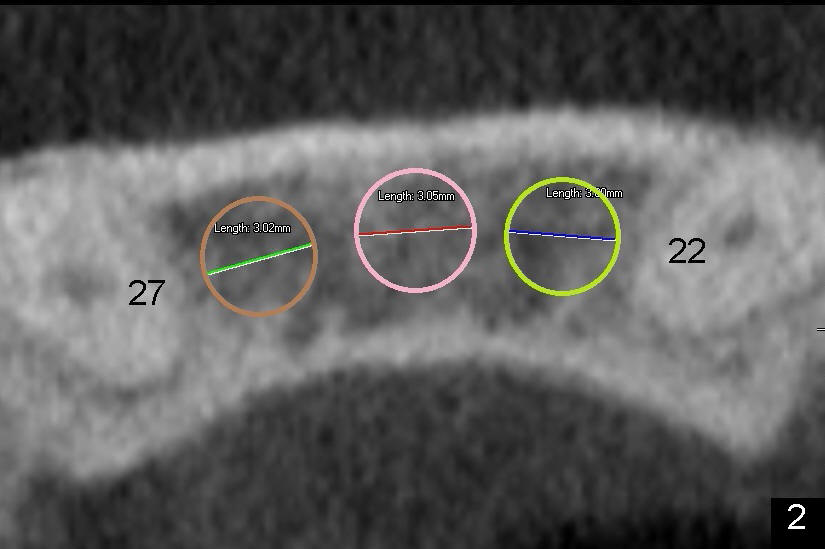

Kent has lost four of the lower incisors (Fig.1 between #22 and 27, S: stent for CT scan). It is planned to place two or three 3.0 mm one piece implants (Fig.2 axial section at root level). Intraop PA shows that one of 1.5 mm pilot drills is close to #22 (Fig.3). The trajectory of this osteotomy was then changed with difficulty; the final PA shows two of 3.0x17 mm one piece implants (Fig.4). Postop, the patient is doing fine. To get the best trajectory, we will penetrate the bone half distance of the intended length with 1.5 mm pilot drills, take PA to see how the angulation is and how close to the adjacent tooth and finish the osteotomy appropriately.